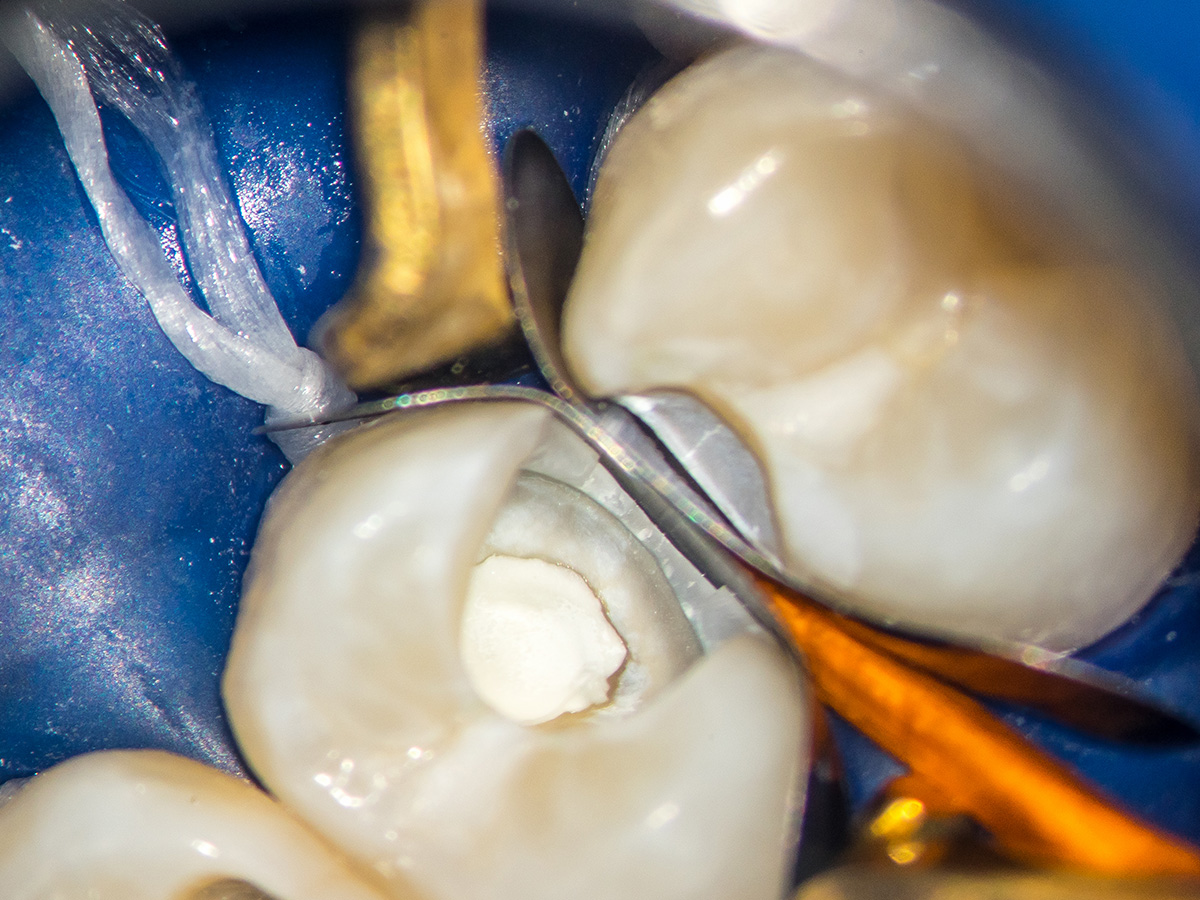

Partielle Pulpotomie mit Bioceramics-Abdeckung und Activa-Deckung

Eine 16-jährige Patientin erschien mit einer ausgeprägten CP bei reversibler Pulpitits in unserer Praxis. Nach einem Aufklärungsgespräch haben wir uns für eine partielle Pulpotomie mit Bioceramics-Abdeckung und ACTIVA-Deckfüllung entschieden. Die Bildreihe zeigt das Vorgehen, das Recall-Bild der Füllung ist fünf Monate alt.

Abbildung 2

Ausgangssituation.

Abbildung 3

Grobe Umrissform. Eröffnung der Kavität an 24.